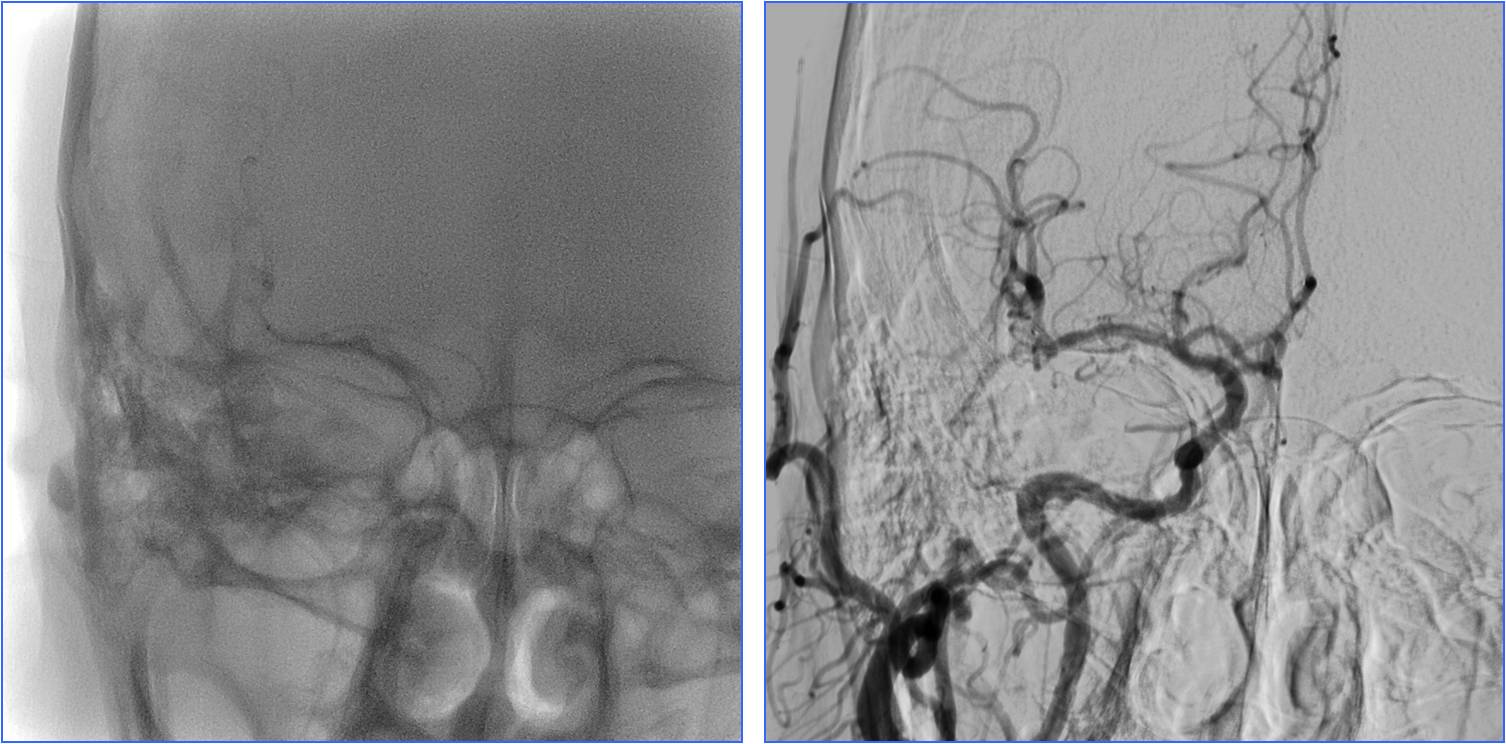

▼左椎动脉颅内段闭塞,脊髓前动脉代偿

▼右椎动脉颅外段闭塞

▼取栓后左椎动脉V4段残留狭窄

▼球囊成形,狭窄改善,不能维持

▼Wingspan支架置入

Case6 术后呼吸功能衰竭

》54岁,男,既往脑梗死、高血压病、糖尿病

》因头晕伴呕吐2天,9:50到达急诊

》10:08完成头CT检查

》15:30突发心跳骤停,行心肺复苏、气管插管

》NIHSS 30分

》15:55头MRA检查

》17:00行股动脉穿刺

》18:50结束手术

》术后24h NIHSS 10分